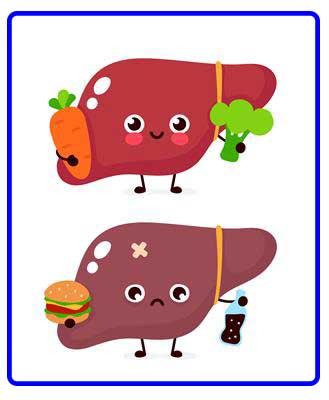

کبد چرب یک عارضه پاتولوژیک است که عملا در زیر میکروسکوپ مشاهده می شود و تعریف آن عبارت است از اینکه در داخل سلول های کبد رسوبات چربی دیده می شود کبد چرب یکی از بیماری های کبد و دستگاه گوارش به حساب می آید که میزان شیوع آن در حال افزایش است. در این مقاله همه چیز در مورد بیماری کبد چرب و راه های تشخیص آن برای شما شرح می دهیم.

بروز بیماری کبد چرب ممکن است ناشی از دلایل مختلفی باشد که مهم ترین آنها شامل موارد زیر می شود:

• تغذیه

• شیوه زندگی

• اضافه وزن

• چربی خون بالا

• قند خون بالا

• مصرف الکل

در بسیاری از موارد، تغییر سبک زندگی می تواند به بهبود این بیماری کمک کند. در پیشگیری از ابتلا به بیماری کبد چرب بهتر است موارد زیر ر ا رعایت کنید:

می دانیم که دلیل کبد چرب، رژیم غذایی نامناسب است که حداقل با استفاده از رژیم صحیح قابل جبران می باشد.